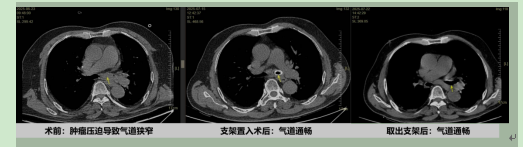

肿瘤压迫导致气道闭塞,支架植入迅速开通气道。